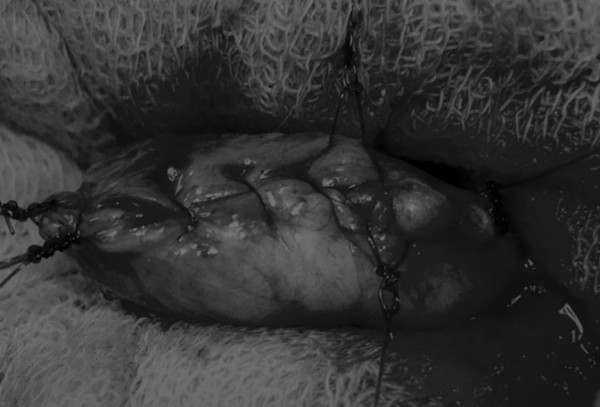

膀胱创面采用单丝合成可吸收缝线缝合,采用外科医生习惯的缝合方式,但注意不要刺穿黏膜层(图6、图7)。

图6 使用简单的连续缝合。尽量不要用针刺穿黏膜层(箭头),以免缝线与尿液接触

图7 缝线应带入足够的切口两侧的膀胱组织,以确保在膀胱充盈时,没有伤口裂开

关膀胱后,将无菌盐水注入膀胱腔内,检查是否有渗漏(图8)。